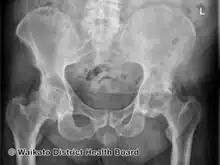

AP Pelvis

In psoriatic arthritis, pain can occur in the area of the sacrum (the lower back, above the tailbone),[3] as a result of sacroiliitis or spondylitis, which is present in 40% of cases. Pain can occur in and around the feet and ankles, especially enthesitis in the Achilles tendon (inflammation of the Achilles tendon where it inserts into the bone) or plantar fasciitis in the sole of the foot.[3]